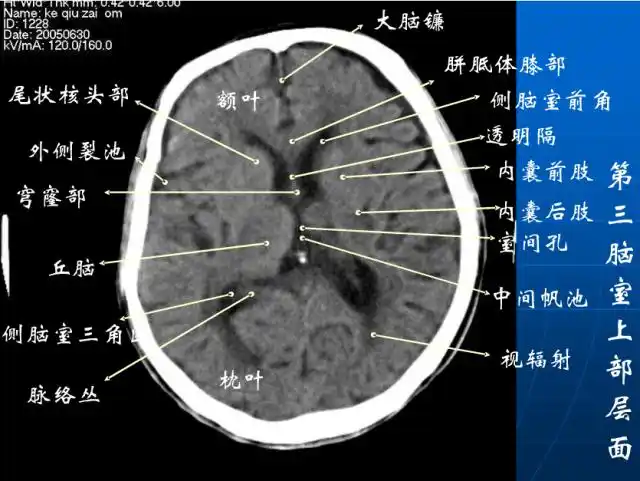

头颅ct解剖与常见出血梗死判读